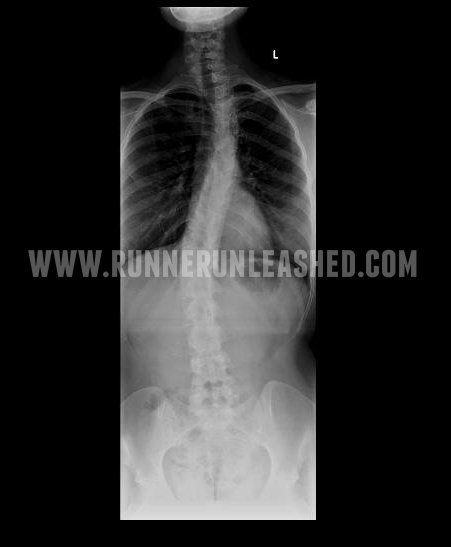

Scoliosis is a term used to describe any abnormal, sideways curvature of the spine. Viewed from the back, a typical spine is straight. When Scoliosis occurs, the spine can curve in many ways. Most commonly into an “S” shape. Curvature of the spine usually occurs when you are growing or going through puberty. In rare cases, Scoliosis can be caused by conditions such as cerebral palsy and muscular dystrophy, the cause of most scoliosis is unknown.

I’d love to say that the Adam’s Forward Bend test will be the only one, but that is just the beginning. The doctor you see will have you do multiple tests,, including x-rays, in some causes MRIs. He will be testing your neurological responses as well. Since the spine includes so many nerves and muscles that go to your brain, it all must be checked. It’s usually are where the doctor asks you to push and resist with different muscles in your legs, feet, arms and hands.

X-rays are a must. No matter the severity of your curve. An x-ray can tell a doctor exactly how much of your spine is curved and they will measure it in degrees.